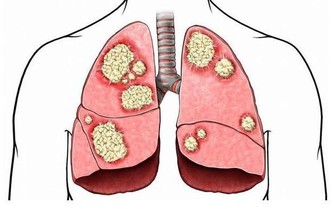

從秋分開始,天氣慢慢轉涼,晝夜溫差較大,氣候變化也無規律,是各種疾病的高發季節。同時,因為天氣乾燥,易出現咽乾、舌乾、少津、乾咳、少痰、皮膚乾裂等現象,也就是中醫學所說的“秋燥”。

需要注意的是,同樣是秋燥,也有溫燥、涼燥之分。一般而言,從秋分開始,人們的秋燥症狀多屬於涼燥。秋分前還有暑熱餘氣,多見溫燥;秋分後,秋風陣陣加上氣溫多變,開始出現涼燥,通常會有頭痛發熱、鼻塞流涕、唇燥咽乾、乾咳連連等症狀。